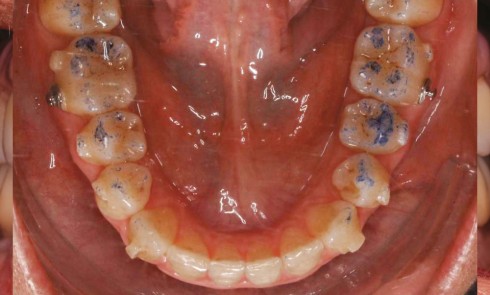

ODF, Parodontologie

Article réservé à nos abonnés Enfant patient parodontal

L’enfant est-il à risque de maladie parodontale ? Il existe une susceptibilité plus faible au développement de l’inflammation gingivale chez...